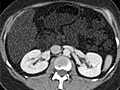

A computed tomography (CT) scan uses X-rays to make detailed pictures of structures inside of the body.

A CT scan can be used to study all parts of your body, such as the chest, belly, pelvis, or an arm or leg. It can take pictures of body organs, such as the liver, pancreas, intestines, kidneys, bladder, adrenal glands, lungs, and heart. It also can study blood vessels, bones, and the spinal cord.

- Abdomen. A CT scan of the abdomen can find cysts, abscesses, infection, tumors, an aneurysm, enlarged lymph nodes, foreign objects, bleeding in the belly, diverticulitis, inflammatory bowel disease, and appendicitis.

- Urinary tract. A CT scan of the kidneys, ureters, and bladder is called a CT KUB or CT urogram. This type of scan can find kidney stones, bladder stones, or blockage of the urinary tract. A special type of CT scan, called a CT intravenous pyelogram (IVP), uses injected dye (contrast material) to look for kidney stones, blockage, growths, infection, or other diseases of the urinary tract.